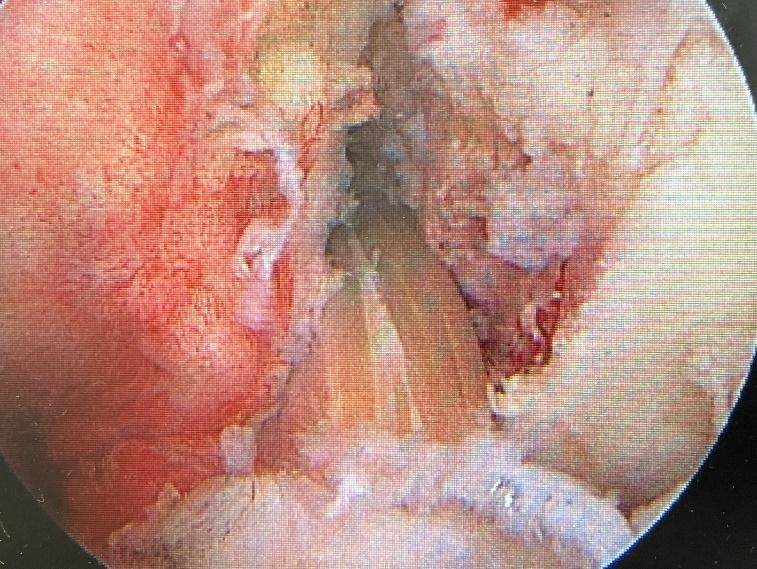

上の写真のように、前十字靱帯はもともとテープ状となっており、捻れた状態で大腿骨(太ももの骨)と脛骨(すねの骨)に付着しています。再建術も、2本の屈筋腱を交差させて捻るように固定したり、膝蓋腱の形状特性を生かして固定したりすることで、本来の前十字靱帯の構造により近づけることができます。